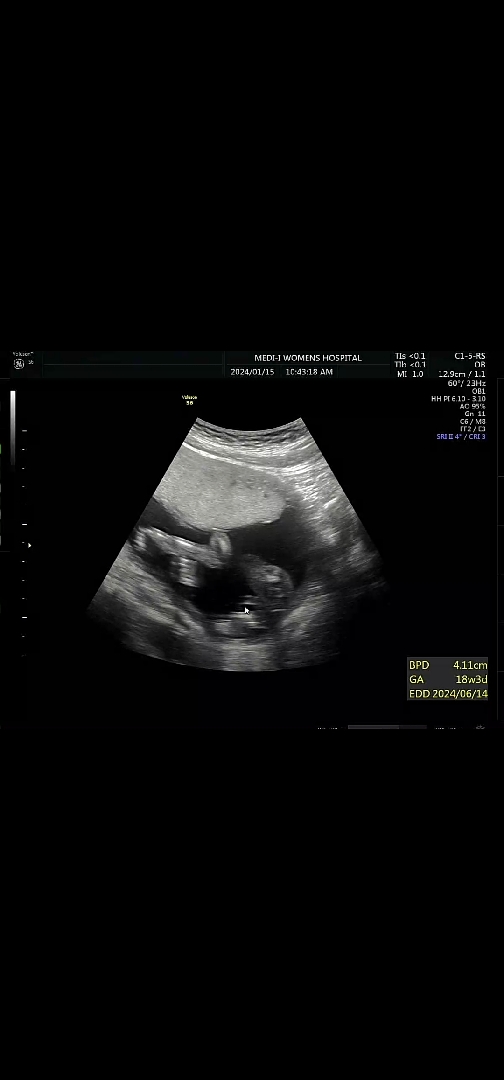

17주차 성별 초음파 아들? 탯줄??

오늘 17주차 초음파 보고 왔는데 조금 보려하면 애기가 몸을 비틀어서 성별 확답을 못받고 왔네요ㅜㅜ 원장님은 지금으로썬 아들인거 같지만 확실한건 한달 뒤에 보자셨어요 그때까지 어떻게 기다리나요😭😭 저기 마우스로 가리킨 저 부분이 혹시 🌶인가요? 사진에서 애기 팔이 보이는 걸로 봐선 다리 사이를 찍은게 아닌거 같아요 어찌나 협조를 안해주던지 그나마 저 사진이 최선이네요ㅎㅎ... 탯줄인거 같기도 하고 성기인거 같기도하고 전 긴가민가 헷갈리는데 어떻게 생각하세요??

긴가민가해요 ㅠㅠㅠ 17주인데,, 더 기다려보셔야겠어요 ㅠㅠㅠ